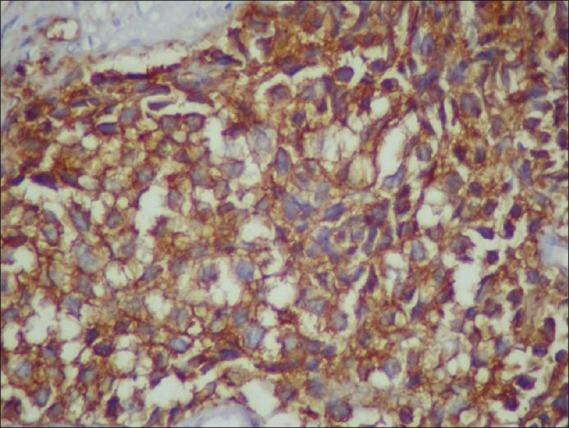

Peripheral primitive neuroectodermal tumor (PNET) of the female genital tract, particularly those in the vaginal and paravaginal region, are extremely rare. A 36-year-old woman presented with clinical features similar to that of a case of cervical fibroid. It was only after surgery that the histopathology suggested it to be a malignant round cell tumour and was CD99 positive. She underwent adjuvant chemotherapy with the Ifosfamide and Etoposide alternating with Vincristine, Doxorubicin, and Cyclophosphamide regime and radical radiotherapy. She is disease free at 12 months of follow-up. The importance of immunostaining and adequate histopathology report lies in the fact that the correct diagnosis thus achieved enabled us to manage a rare case of paravaginal PNET with a multimodality approach.

女性生殖道外周原始神经外胚层肿瘤(PNET),尤其是阴道和阴道旁区域的此类肿瘤极为罕见。一名36岁女性的临床表现与宫颈肌瘤病例相似。直到手术后,组织病理学检查才提示其为恶性圆形细胞瘤且CD99呈阳性。她接受了异环磷酰胺和依托泊苷交替联合长春新碱、多柔比星及环磷酰胺方案的辅助化疗以及根治性放疗。随访12个月时她无疾病复发。免疫染色及充分的组织病理学报告的重要性在于,由此获得的正确诊断使我们能够采用多模式方法处理一例罕见的阴道旁PNET病例。